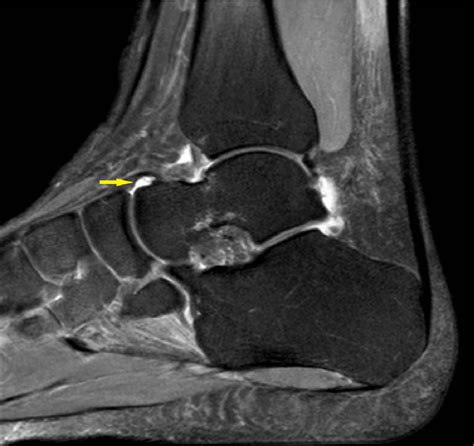

MRI Provides detailed visualization of soft tissues, ligaments, and cartilage to identify tears or inflammatory changes.

Ultrasound Highly effective for identifying and quantifying the amount of fluid in the joint space.